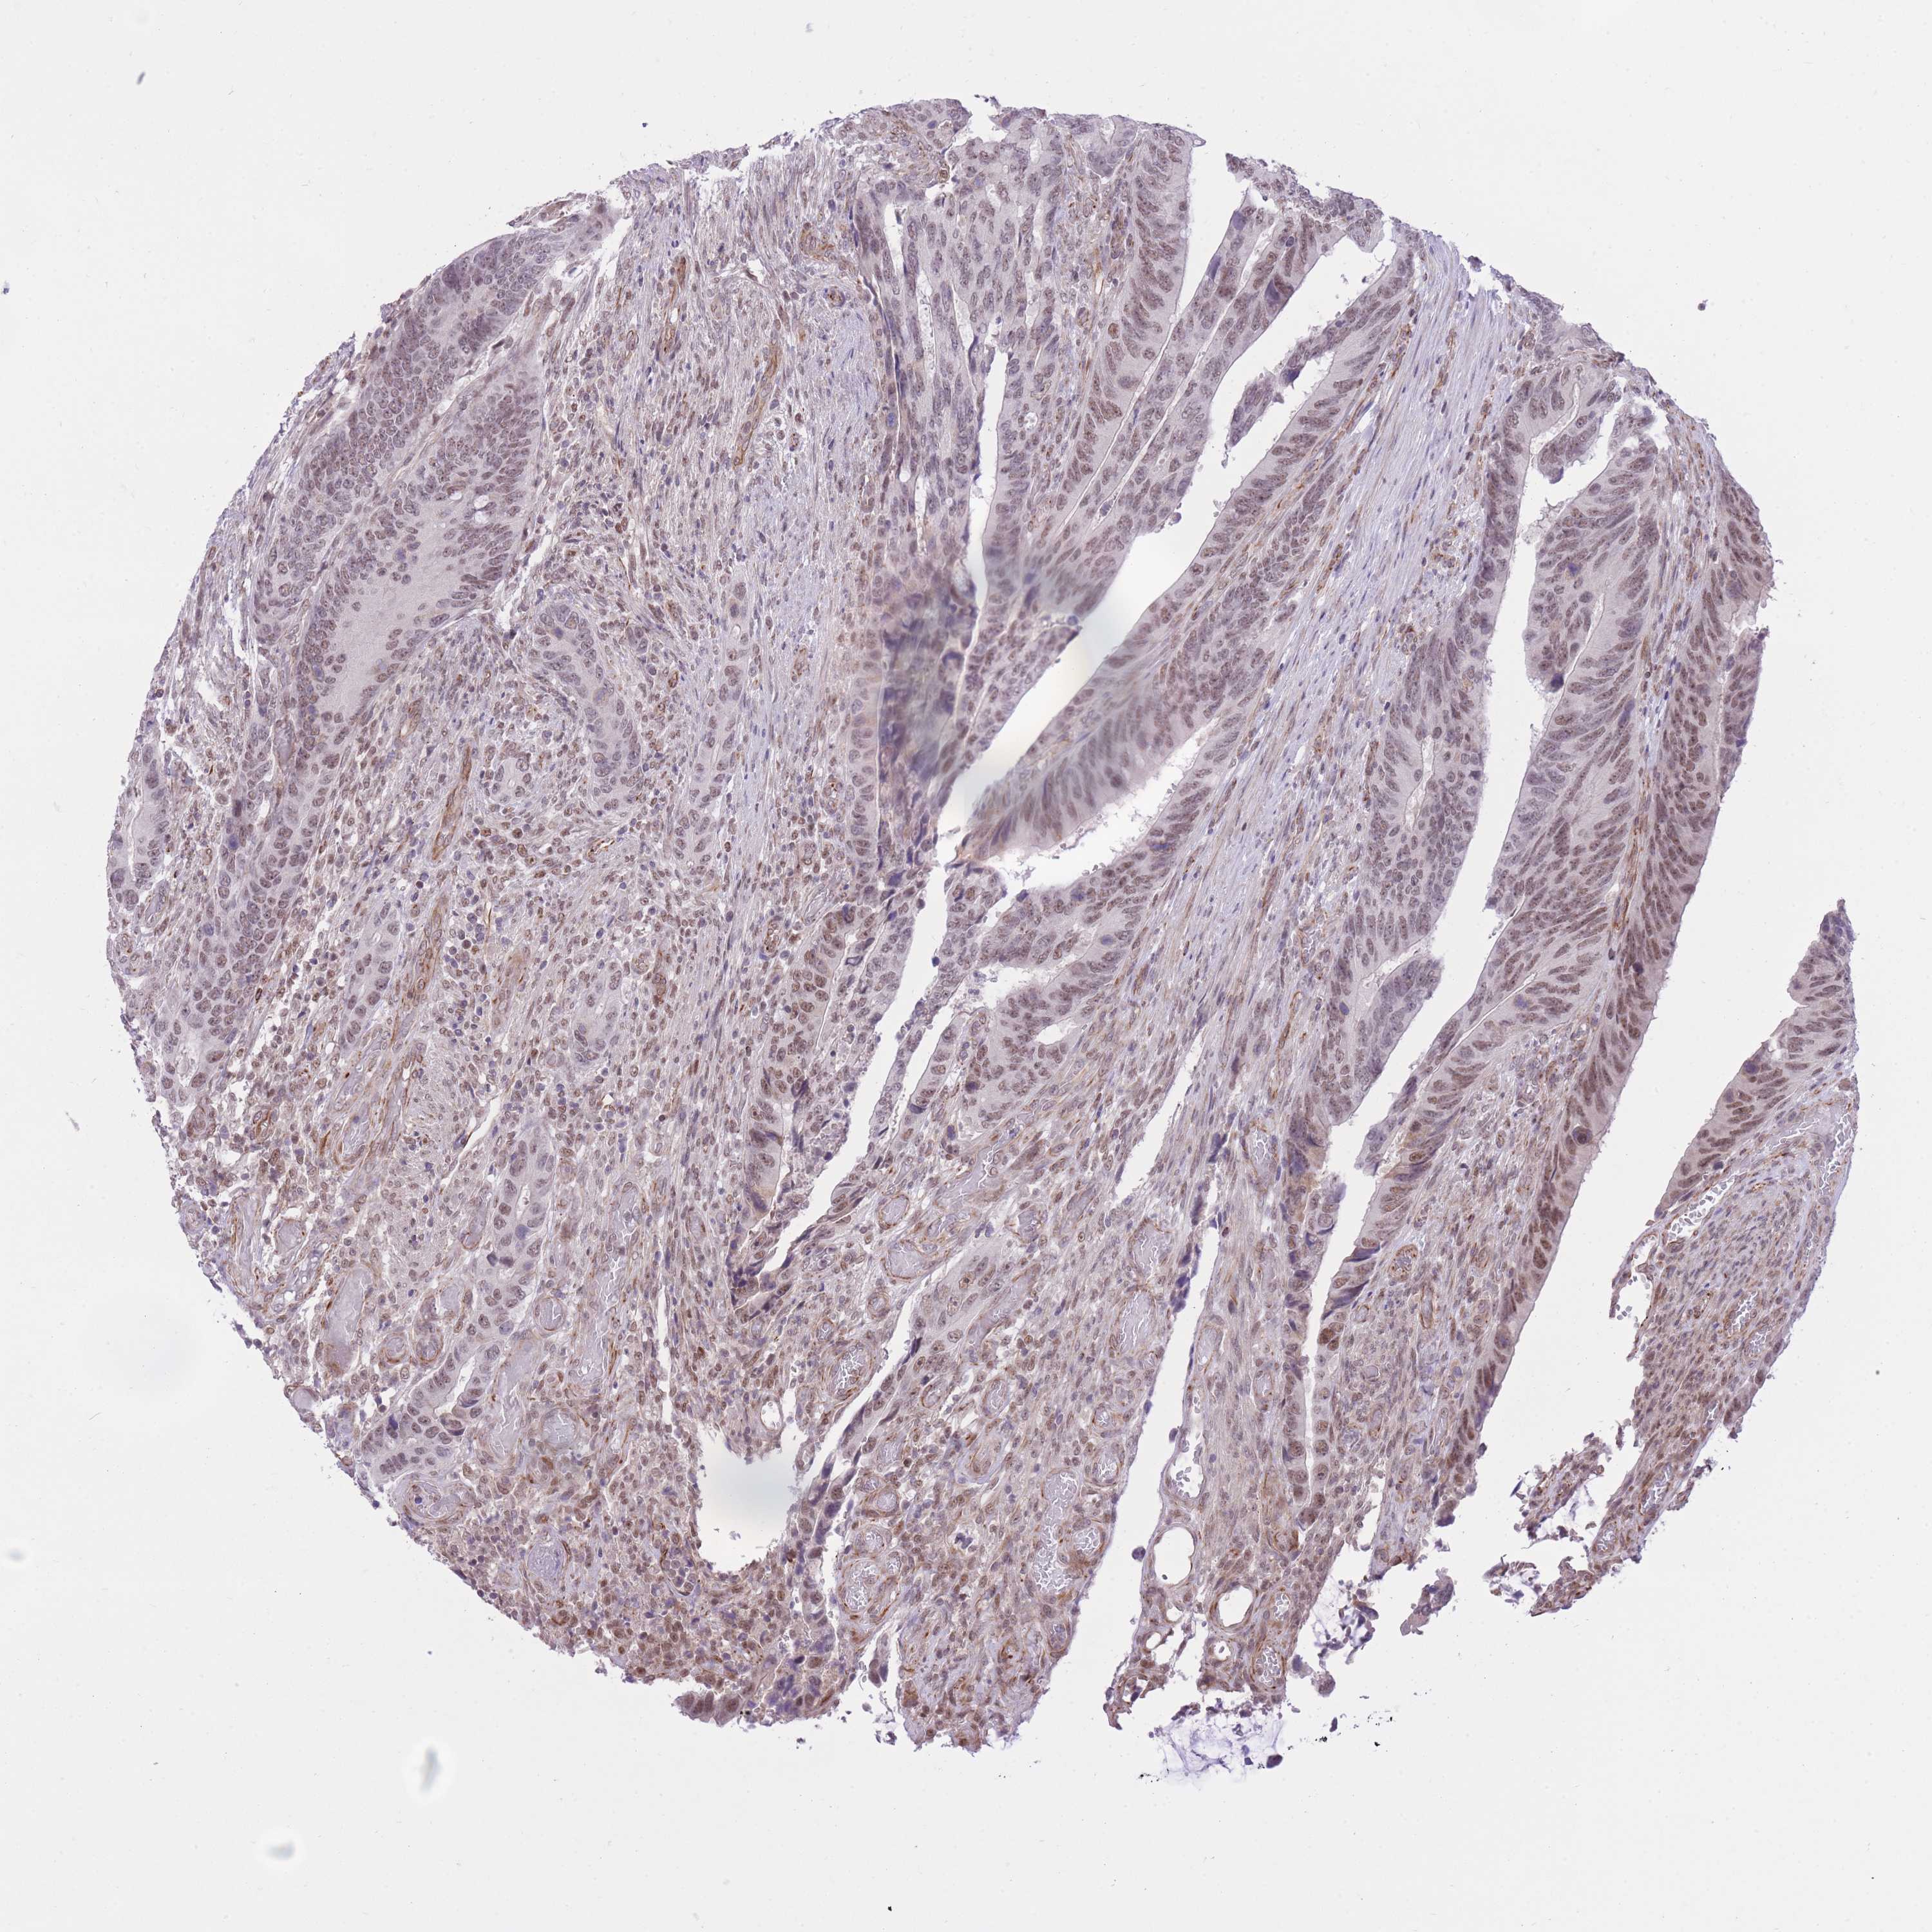

CANCER COLORECTAL CANCER Show tissue menu

COAD TCGA COAD VALIDATION READ TCGA READ VALIDATION PROTEIN COAD CPTAC PROTEIN EXPRESSION

ANTIBODIES

AND

VALIDATION

Colorectal cancer

Human cancer

Colon adenocarcinoma

Rectum adenocarcinoma